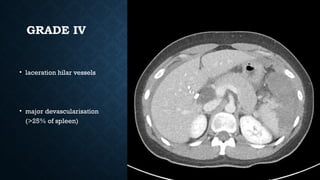

GRADE IV

• laceration hilar vessels

• major devascularisation

(>25% of spleen)

GRADE IV • lacerationhilar vessels • major devascularisation (>25% of spleen)